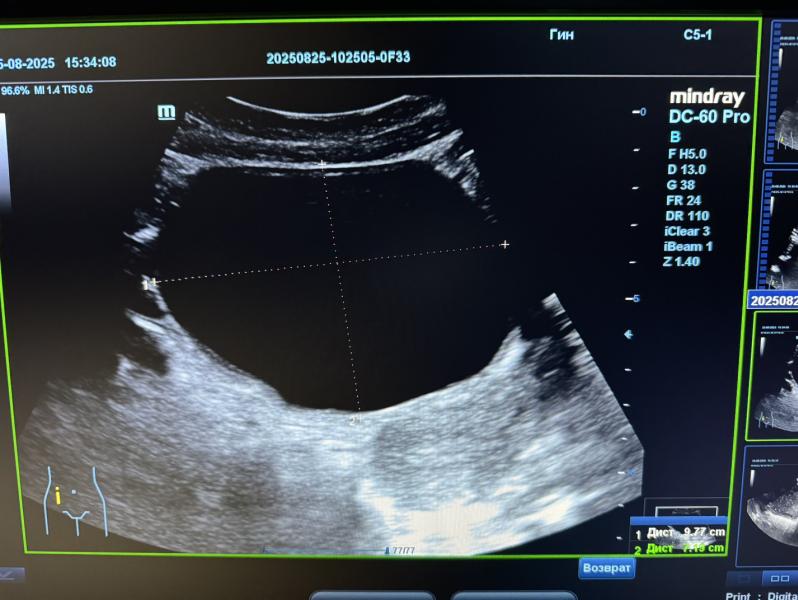

При проведение УЗИ обнаружила ОГРОМНУЮ кисту правого яичника, которая занимает весь малый таз , больше чем мочевой пузырь , матка

Киста размерами 10 см ‼️